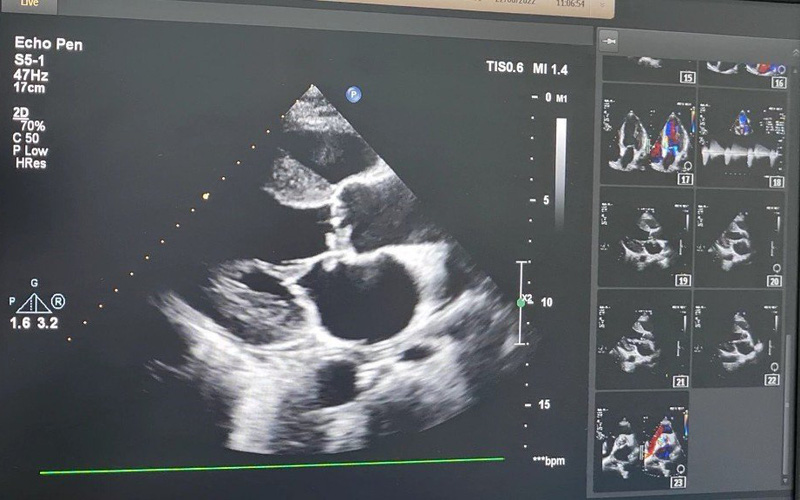

Siêu âm tim anh T. phát hiện cục sùi lớn, gây thủng van và làm hở nặng van hai lá. Ảnh: BVCC